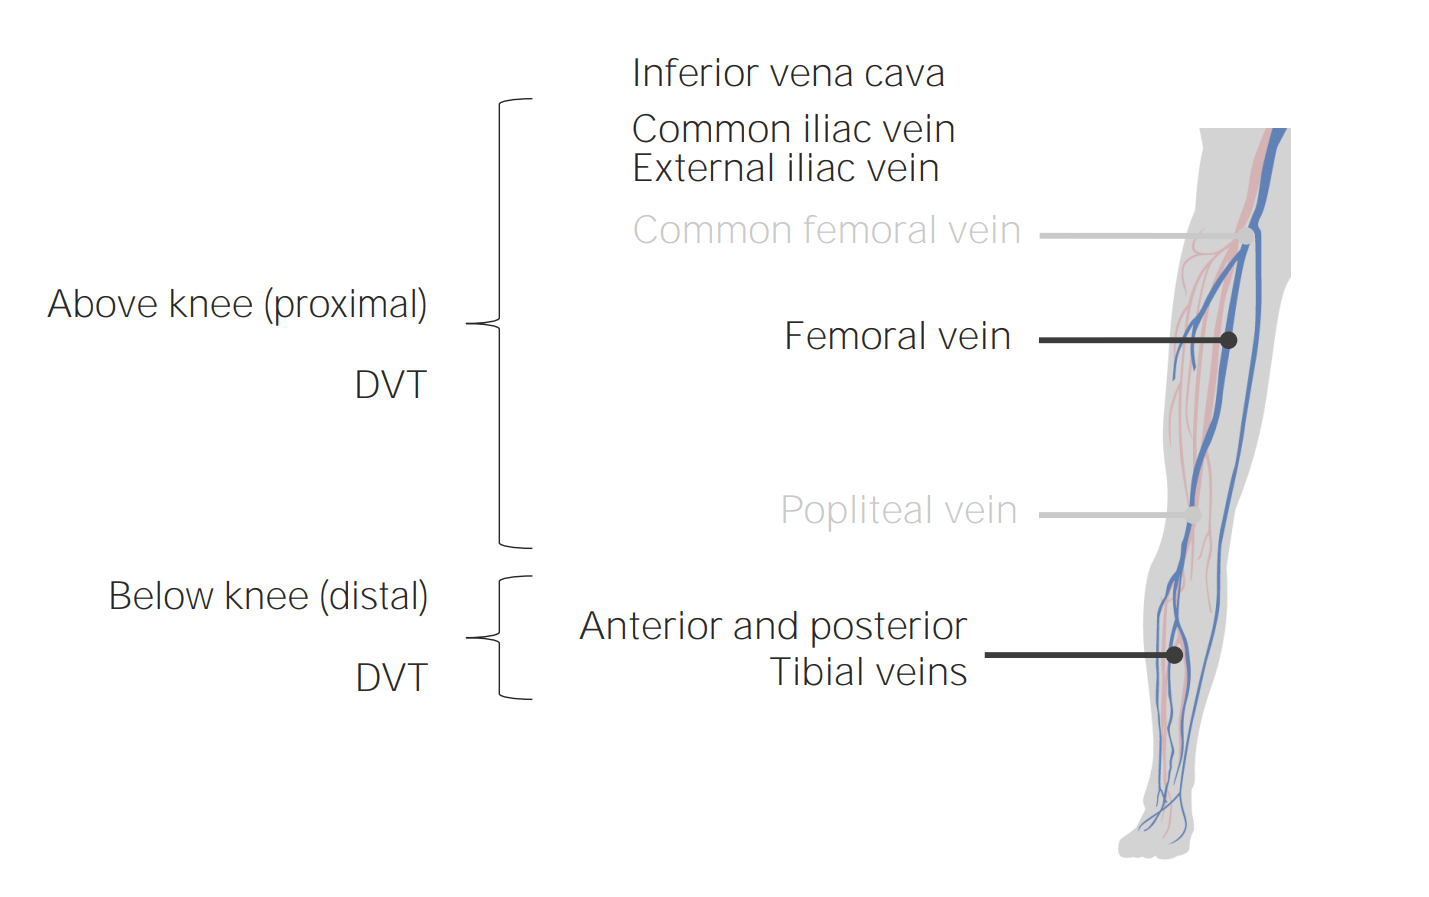

Distal And Proximal Deep Vein Thrombosis | BioRender Science Templates

www.biorender.com

www.biorender.com

Distal Vs Proximal Veins

mavink.com

mavink.com